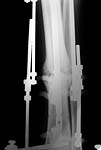

A male 26 y.o. sustained closed tibial shaft fracture after a car accident (pedestrian injury) Feb 7, 2002. In a small local hospital the Ilizarov fixator was applied, reduction was poor. 3 months later it was removed and replaced by plaster cast. The patient reported after ex-fix removal mobility at the site, no wire tract infection. A month later he himself decided to take off the cast. Now walks with cane and limp, marks pain over the site. No obvious mobility found at examination. Recent films (AP and 3/4) attached.

What diagnosis is correct to date? Pseudarthrosis? Delayed union? Something else?

We plan to nail it "as is" with dynamic locking. Is closed osteoclasis necessary here? Should fibular osteotomy be performed? Any other additional measures - bone grafting?